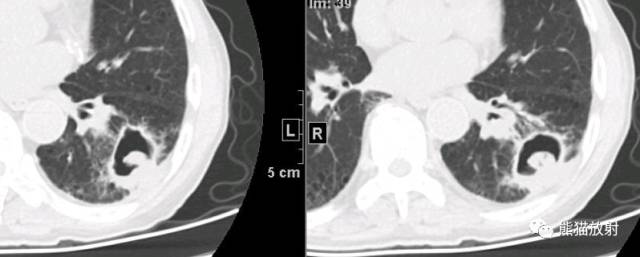

胸部CT-肺窗

俯卧位(下图):洞内球状内容物随体位的变化移位